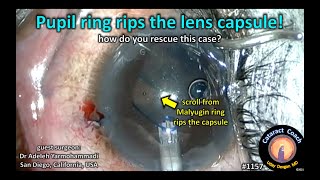

Cataract removal with MiLoop CataractCoach 1157: Malyugin pupil ring rips the lens capsule!

CataractCoach 1157: Malyugin pupil ring rips the lens capsule!

Cataract removal with MiLoop CataractCoach 1157: Malyugin pupil ring rips the lens capsule!

CataractCoach 1157: Malyugin pupil ring rips the lens capsule!